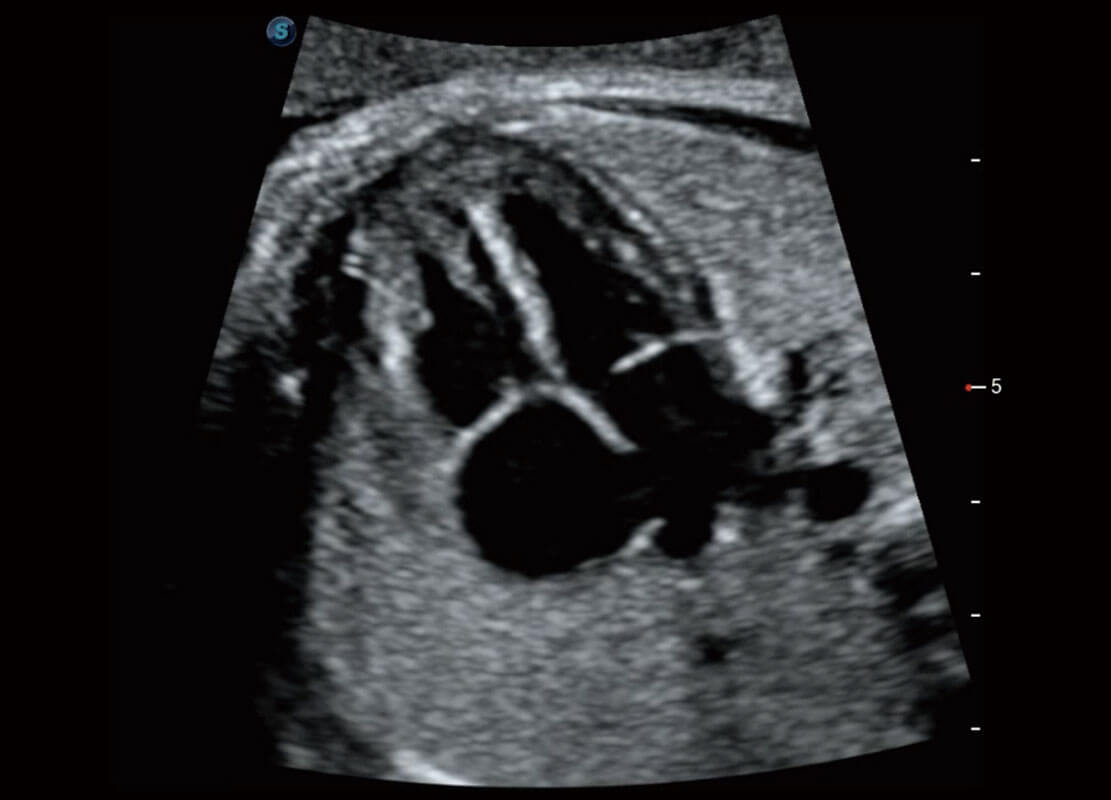

腔内妇科-卵巢

P60在胎儿早孕期超声筛查中为您带来优异的图像质量。

早孕-胎心

高分辨率容积成像-早孕胎儿